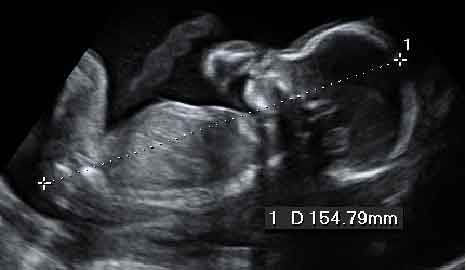

Ecografía bidimensional o 2D

Es la modalidad que se utiliza habitualmente. Los ecos rebotados por las estructuras que atraviesa el haz de ultrasonidos son visualizados como múltiples imágenes secuenciales en escala de grises. [ Ver ecografía bidimensional ]